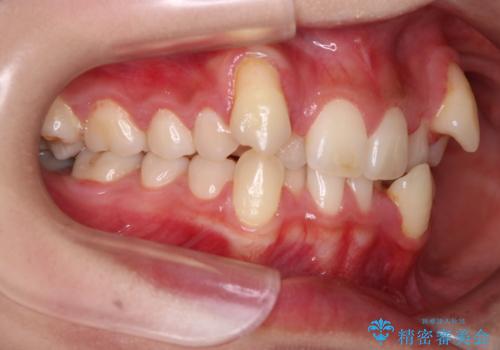

- 八重歯を主訴に来院された患者様です。

インビザラインによる矯正を希望され、今回は移動距離が少なくなるように犬歯を抜歯する治療計画としました。

抜歯矯正において、通常では4番(第一小臼歯)が抜歯の対象となることが多いのですが、今回は3番(犬歯)の歯肉退縮や装置の特性を考慮した治療計画となります。

下顎に関しては、半年ほどワイヤー矯正にてリカバリーを行なっております。